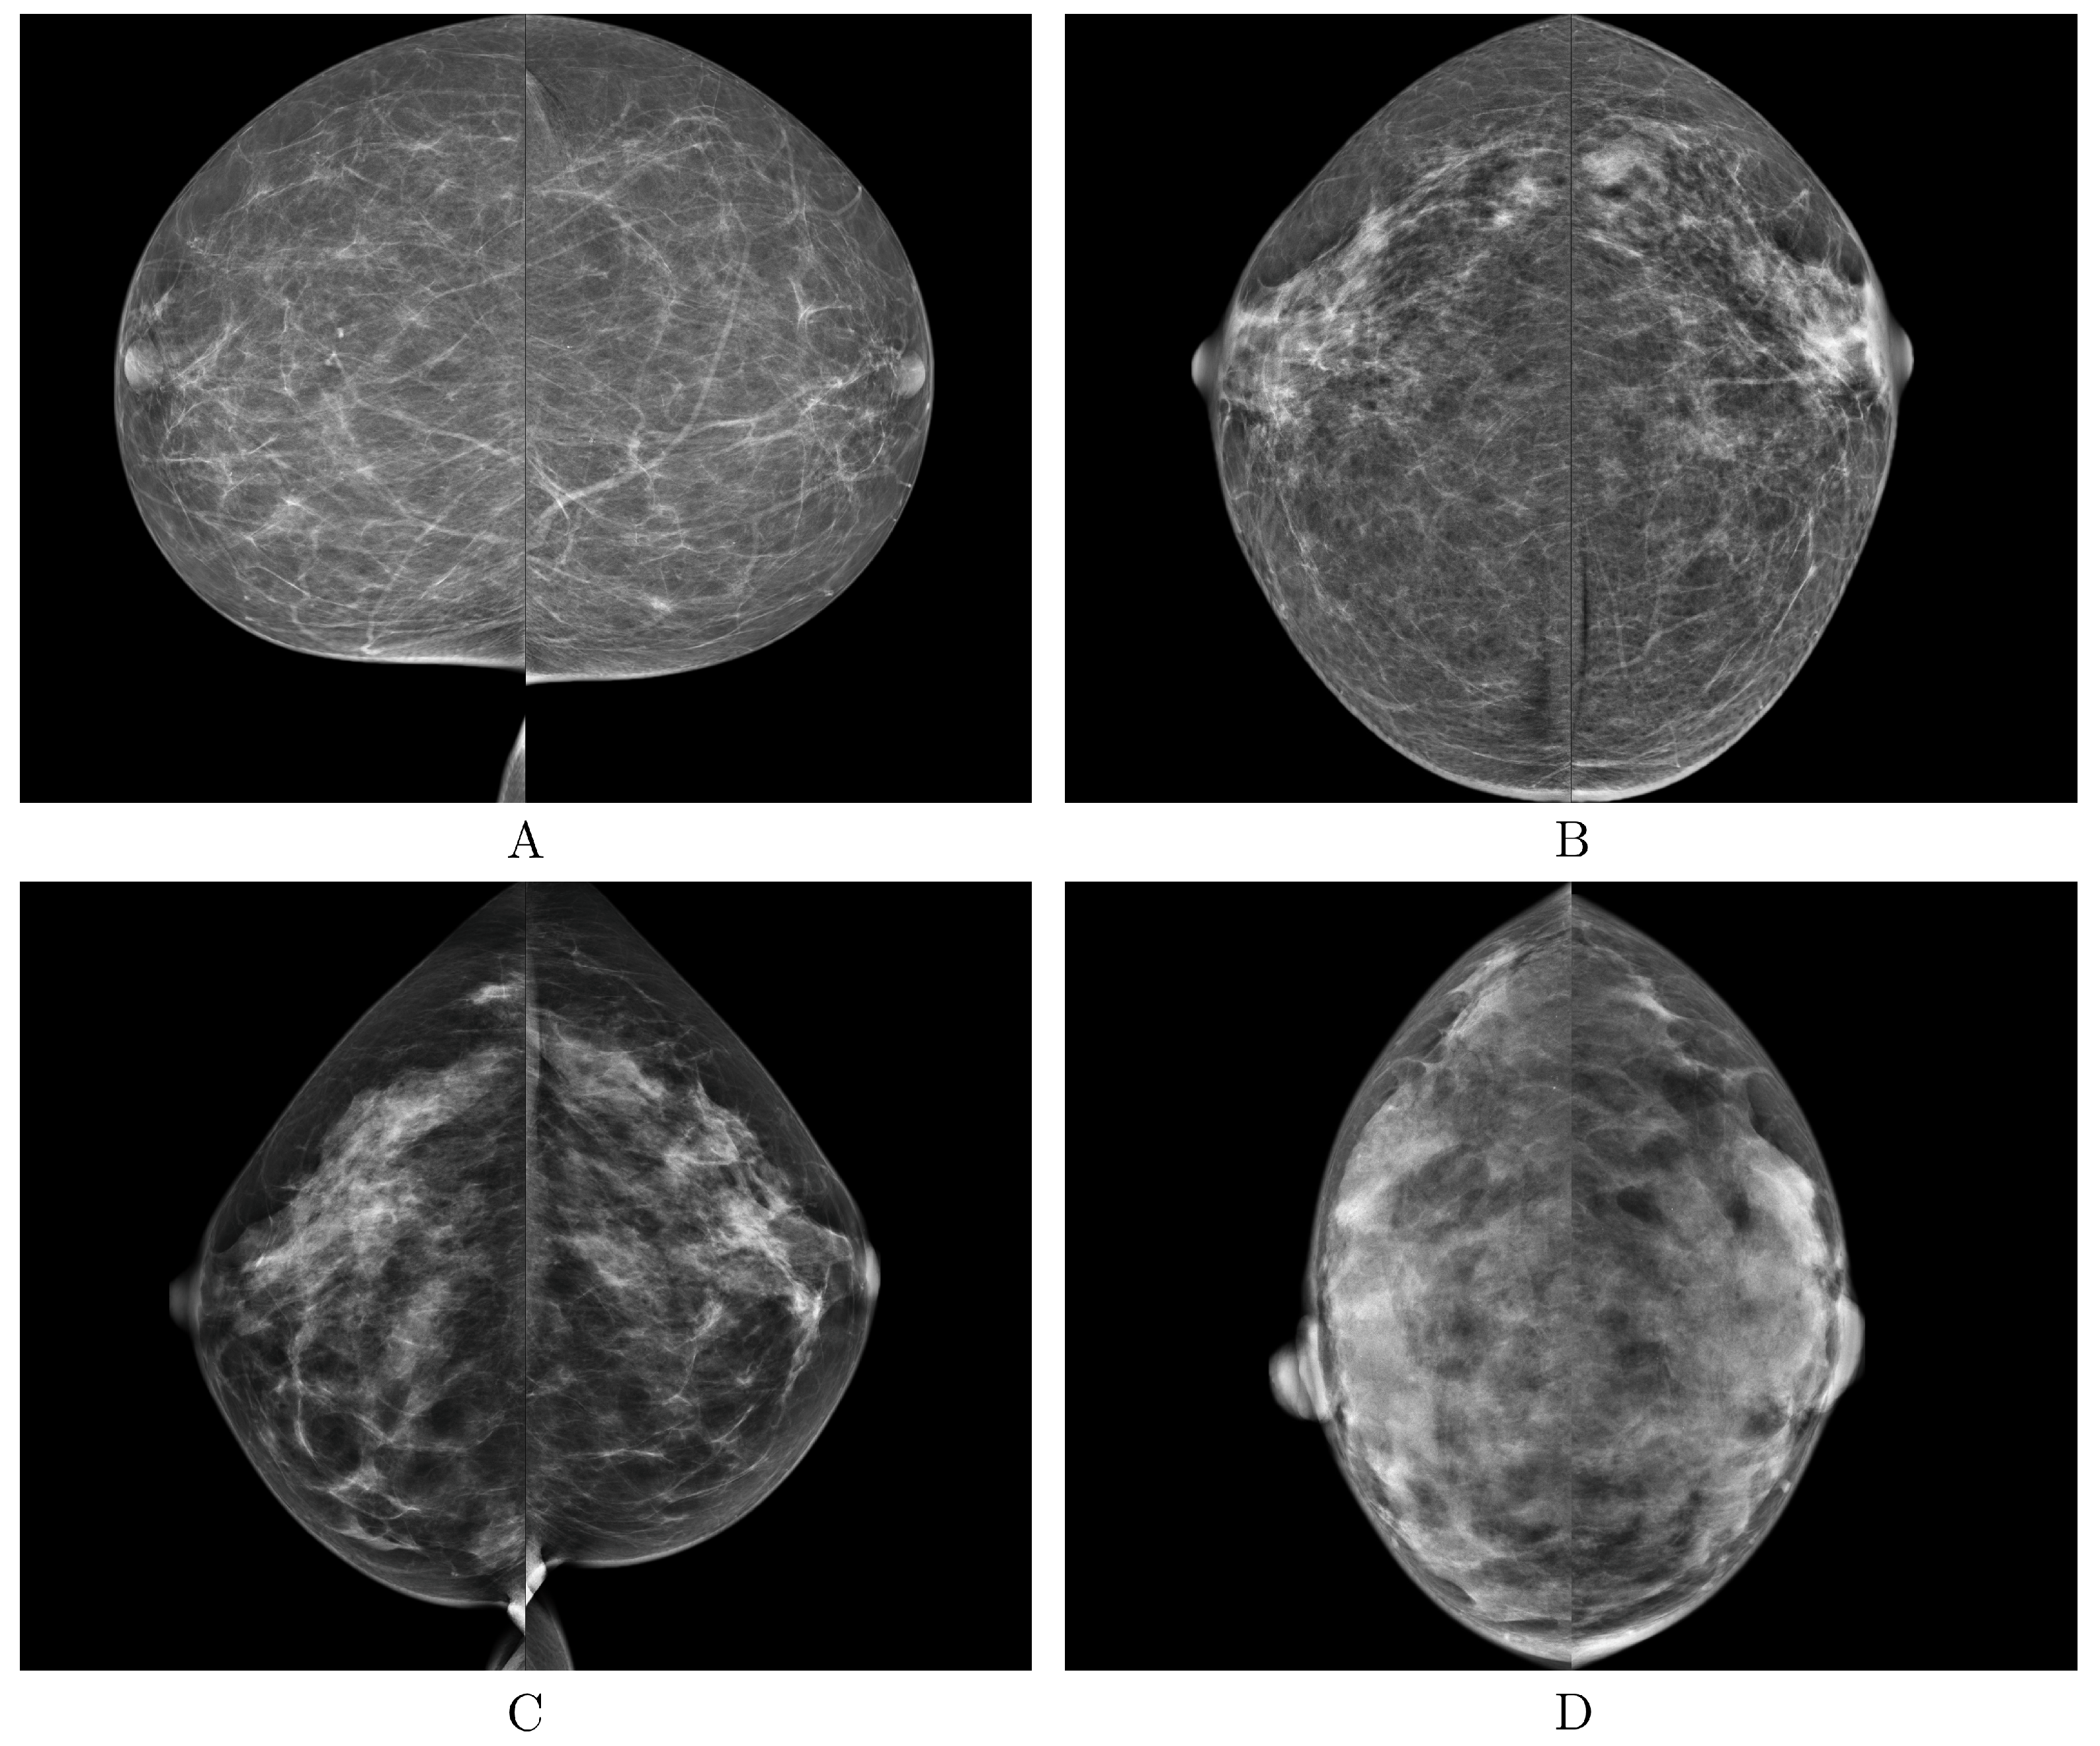

| BI-RADS | Breast Imaging-Reporting and Data System |

| BI-RADS Category | / |

|---|---|

| Class A | 879/3516 |

| Class B | 3212/12,848 |

| Class C | 928/3712 |

| Class D | 111/444 |

| Total | 5130/20,520 |

| Class A | 18/72 |

| Class B | 43/172 |

| Class C | 7/28 |

| Class D | 4/16 |

| Total | 72/288 |